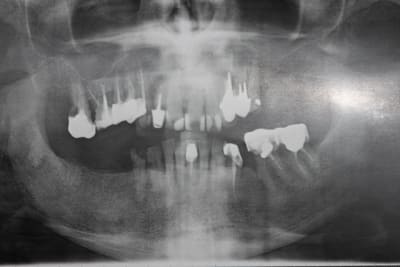

La pano est dégueulasse, à l'époque je n'avais pas encore la mienne, merci les radiologues.

La pano est vraiment dégueu mais traitement idéal pour moi : extraction de tout en haut sauf 12 11 21 22 (13 ? on voit rien) (emax sur dent vivante) et implanto après traitement paro.

Le bas est plus sujet à discussion, mais extraire 36 37 (paro + égressées), composites ou couronnes selon l'atteinte carieuse, et implanto après paro pour les dents manquantes.

En l'occurence, même si pas mal de solutions étaient valables, on en a choisi une plus proche de celle de Thomas Crown. (en vrai, c'est un peu moins moche que sur la pano.)

Pour compléter également, pas de mobilités, hormis 24/25. Pas de lésions furcatoires.

La 16 a été amputée de sa racine MV, mais le patient ne se souvient plus quand.

A ce stade, cela nous permet de confirmer l'absence de lésions furcatoires: tronc radiculaire long de la 16 et anatomie favorables des prémolaires nous ont évité pas mal de difficultés. Du coup, tout est plus simple au niveau paro...

C'est là que je ne suis pas d'accord. On a certes une alvéolyse horizontale autour de 50%, mais encore une fois, aucne lésion furcatoire. Le jour de l'empreinte définitive, il n'y avait plus aucune poche supérieure à 2-3, pas de mobilités, hygiène nickel (malgré le bridge pro, par définition moins lisse que la céramique).

Pour l'endo, j'ai repris 12 13 14, ainsi que 36 37. 15 16 étaient correctes, asyptomatiques depuis 20 ans et étanches (les RCR ont été conservées.)

36 et 37 étaient largement calcifiées, je suis allé aussi loin que possible, mais c'était un peu décevant, ce sont les seules qui m'embêtent un peu.

Pano de contrôle (où je m'aperçois que j'avais laissé un morceau de Fuji entre 36 et 37, honte sur moi, d'où l'intérêt de la radio).